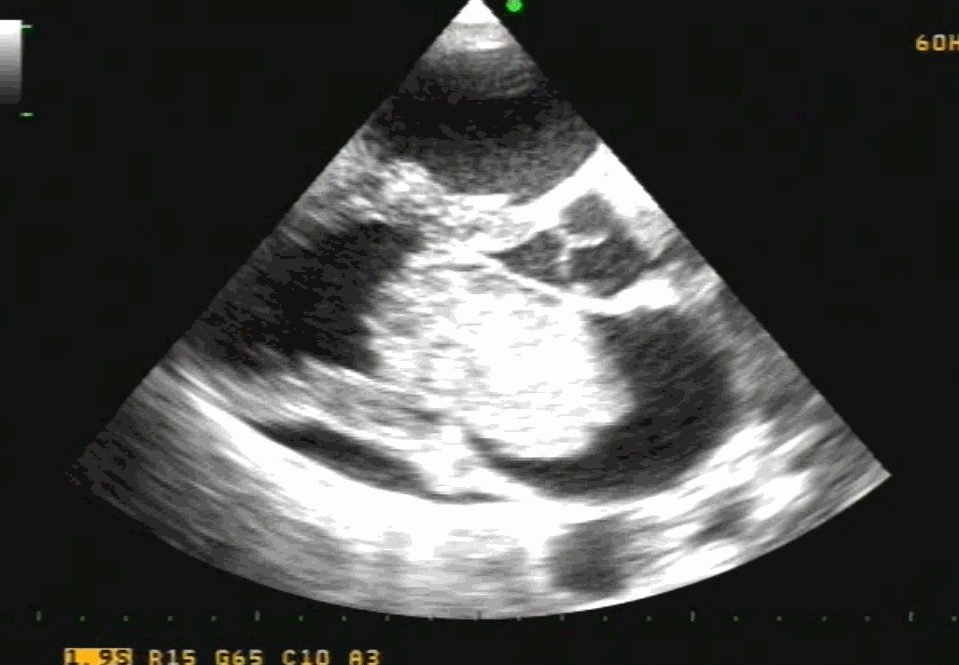

Bicaval view is an Important TEE view to visualize, the LA, IAS, and right atrium. I used to have some trouble getting oriented to this view. Hence this post. It is obtained in the 90-120 degree view at the mid esophageal position. Imagine the patient is lying on his left side and the probe comes from above down between the spine and heart to the LA from within the esophagus. This is the best view to see IAS in the profile.(Subcostal TTE can also do it) Note how the LA hugs the right atrium which is actually an ill-defined (In TEE I mean) common meeting point of both IVC and SVC. Also important is the relationship of RUPV with SVC & the horizontally running RPA sitting right over the top of LA.

The relationship between RUPV and SVC is crucial in device closure of large ASD, especially in sinus venous defect.

Clinical Importance of this view

Very useful in ASD rim morphology especially in the posterosuperior rim.

Delineates clearly the defect boundaries in SVC ASD.

This view doesn’t miss even the smallest PFO (With Contrast )

Can be used to guide IAS puncture in structural heart Interventions.

IVC /SVC mass extension into RA well visualized.